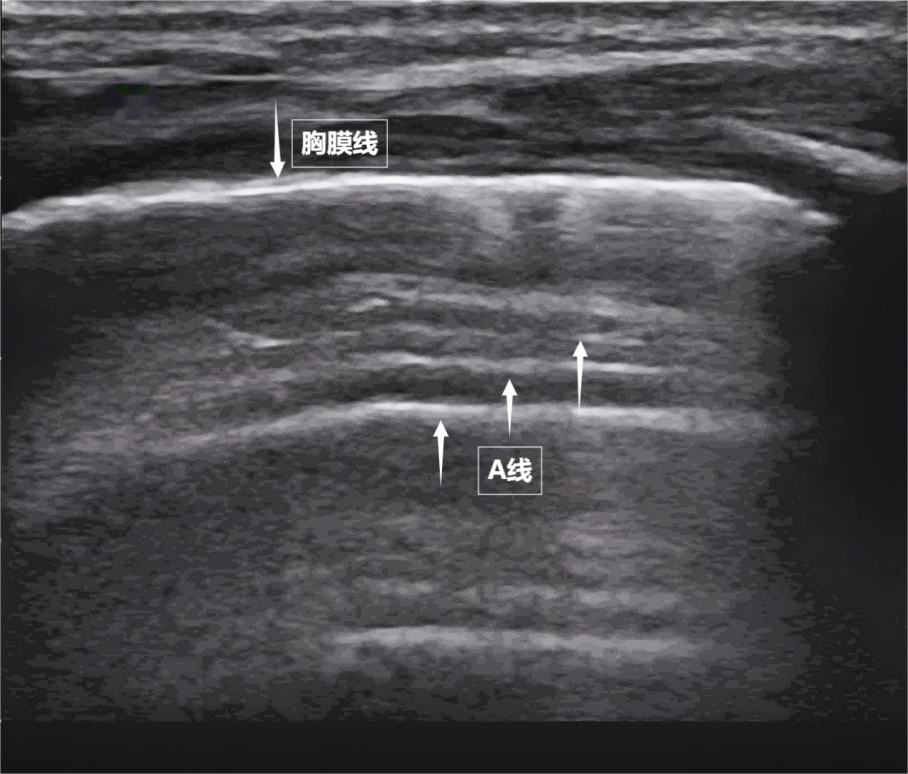

肺,是我们身体里一对日夜不息的“风箱”,藏在胸腔深处,看不见、摸不着,却关乎每一次呼吸质量。医生是如何“看见”肺部状态的?检查方法有不少,但也各有“短板”:X线有辐射,CT不便移动,听诊器依赖医生经验……今天,我们要介绍一种既安全又便捷的“透视眼”——肺部超声。这把“声波探针”正以无辐射、实时动态、床边即查的优势,成为观察肺功能的新窗口。它不留痕迹,却能捕捉肺部细微变化。超声是如何“看见”肺的要理...